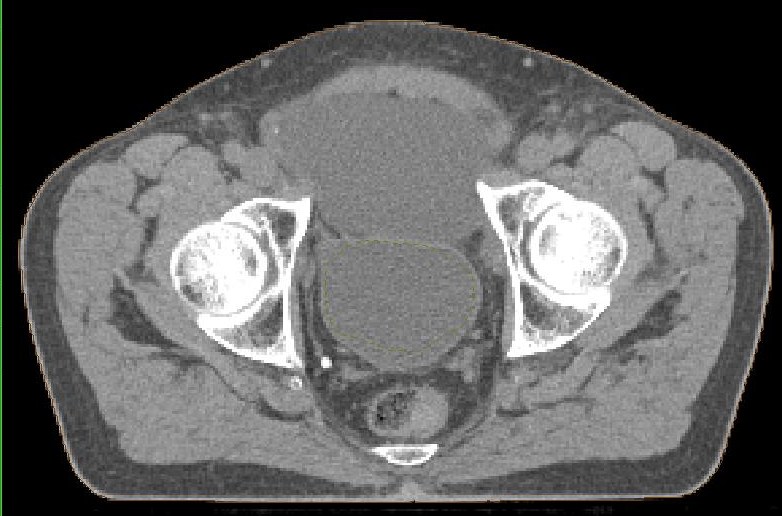

postoperative Lymphozele

Große Lymphozelen nach laparoskopischer pelviner Lymphonodektomie.